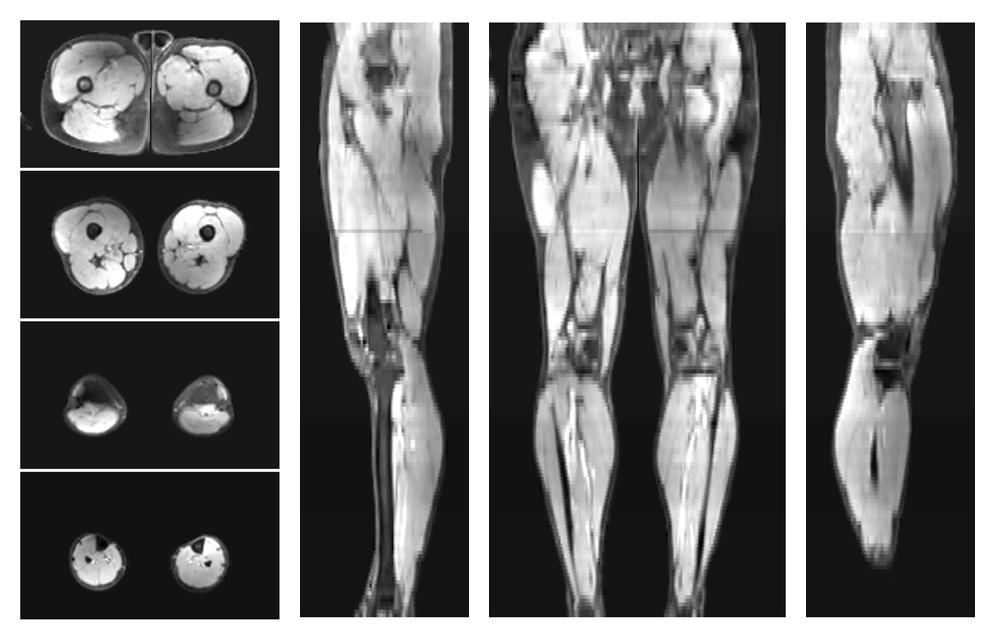

• Out phase image

The out-phase image of the dixon reconstruction for water fat quantification.